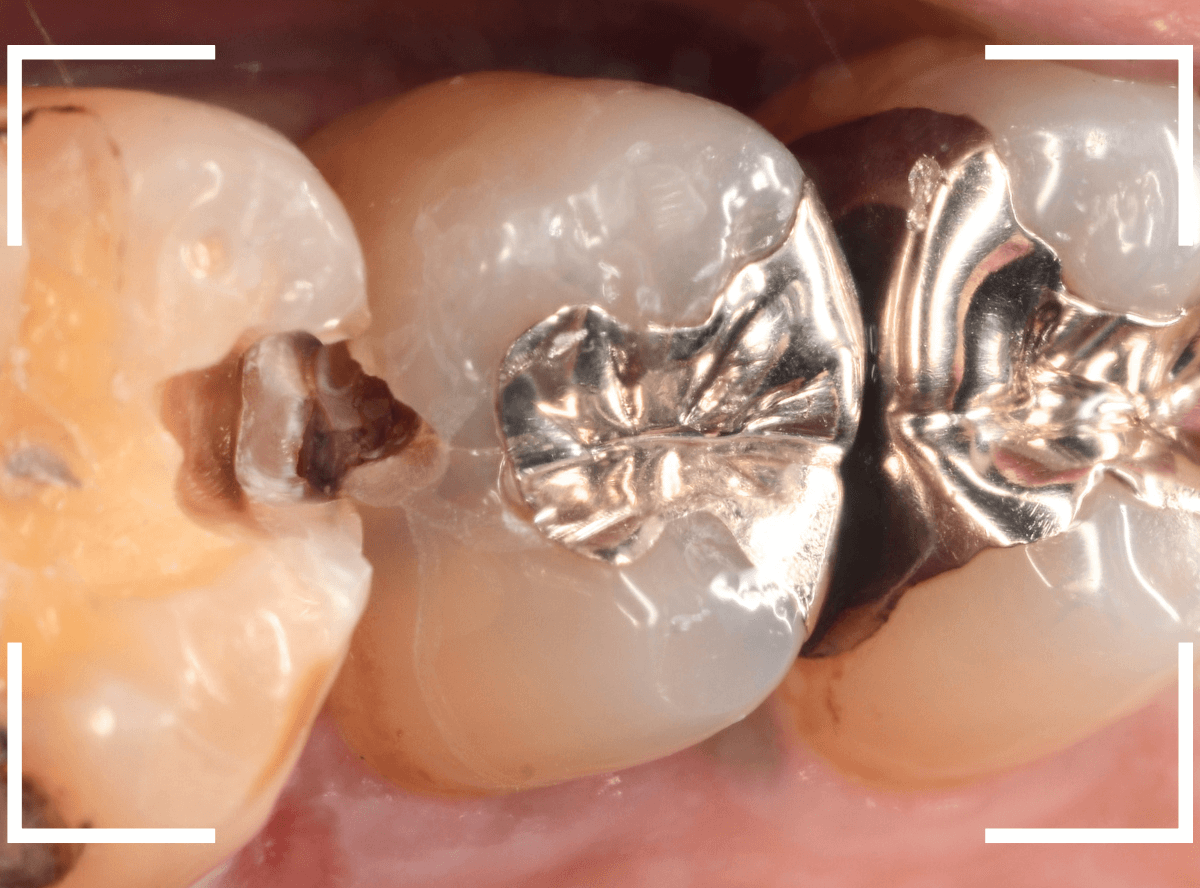

Case.25 レントゲン所見と目視を頼りに、虫歯治療

検査時に〇部、歯と歯の間の小臼歯部に虫歯らしき黒い影があるのが見つかりました。

かなり怪しいですが、メタル・インレーが入ってるので、それが透けている可能性もあります。

レントゲン写真で確認します。

レントゲンでは後ろの大臼歯部の方が虫歯になっているように見え、小臼歯部は問題ないように見えます。

まず大臼歯のインレーを外して、中を調べます。

あれ、インレー直下は虫歯がなさそうです。

レントゲン写真を頼りに、歯を削ると、虫歯が出てきました。

大臼歯の虫歯を削っていくと、手前の小臼歯まで虫歯がつながっていました。

やはり、黒い影は虫歯でした。これは深そうです。

メタル・インレーも外して、虫歯を除去します。

全ての虫歯を除去しました。

レントゲン写真では確認できませんでしたが、手前の小臼歯は深い虫歯でした。

このように、歯と歯の間の虫歯は、深い事が多いです。